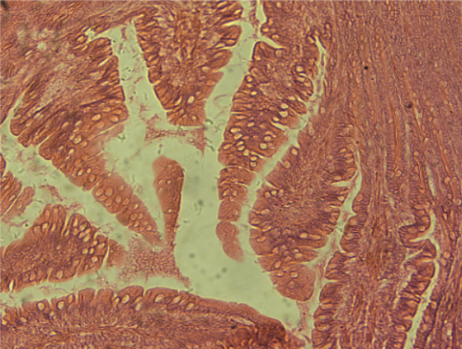

![]() | ![]() | |

肠切片 | 肺切片 |